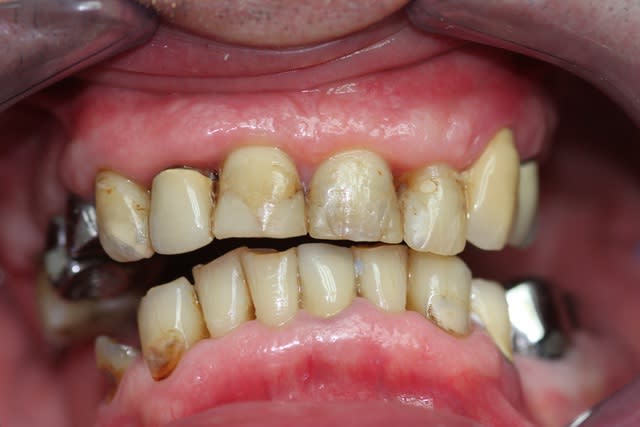

-Pas de photo du visage pré-traitement, le patient ne sourie pas, probablement complexé, et je n'ai pas voulu en rajouter.

-Brossage moyen, ok dès la première séance après enseignement de l'hygiène.

En l'occurence, même si pas mal de solutions étaient valables, on en a choisi une plus proche de celle de Thomas Crown. (en vrai, c'est un peu moins moche que sur la pano.)

Je l'argumenterai avec les photos.